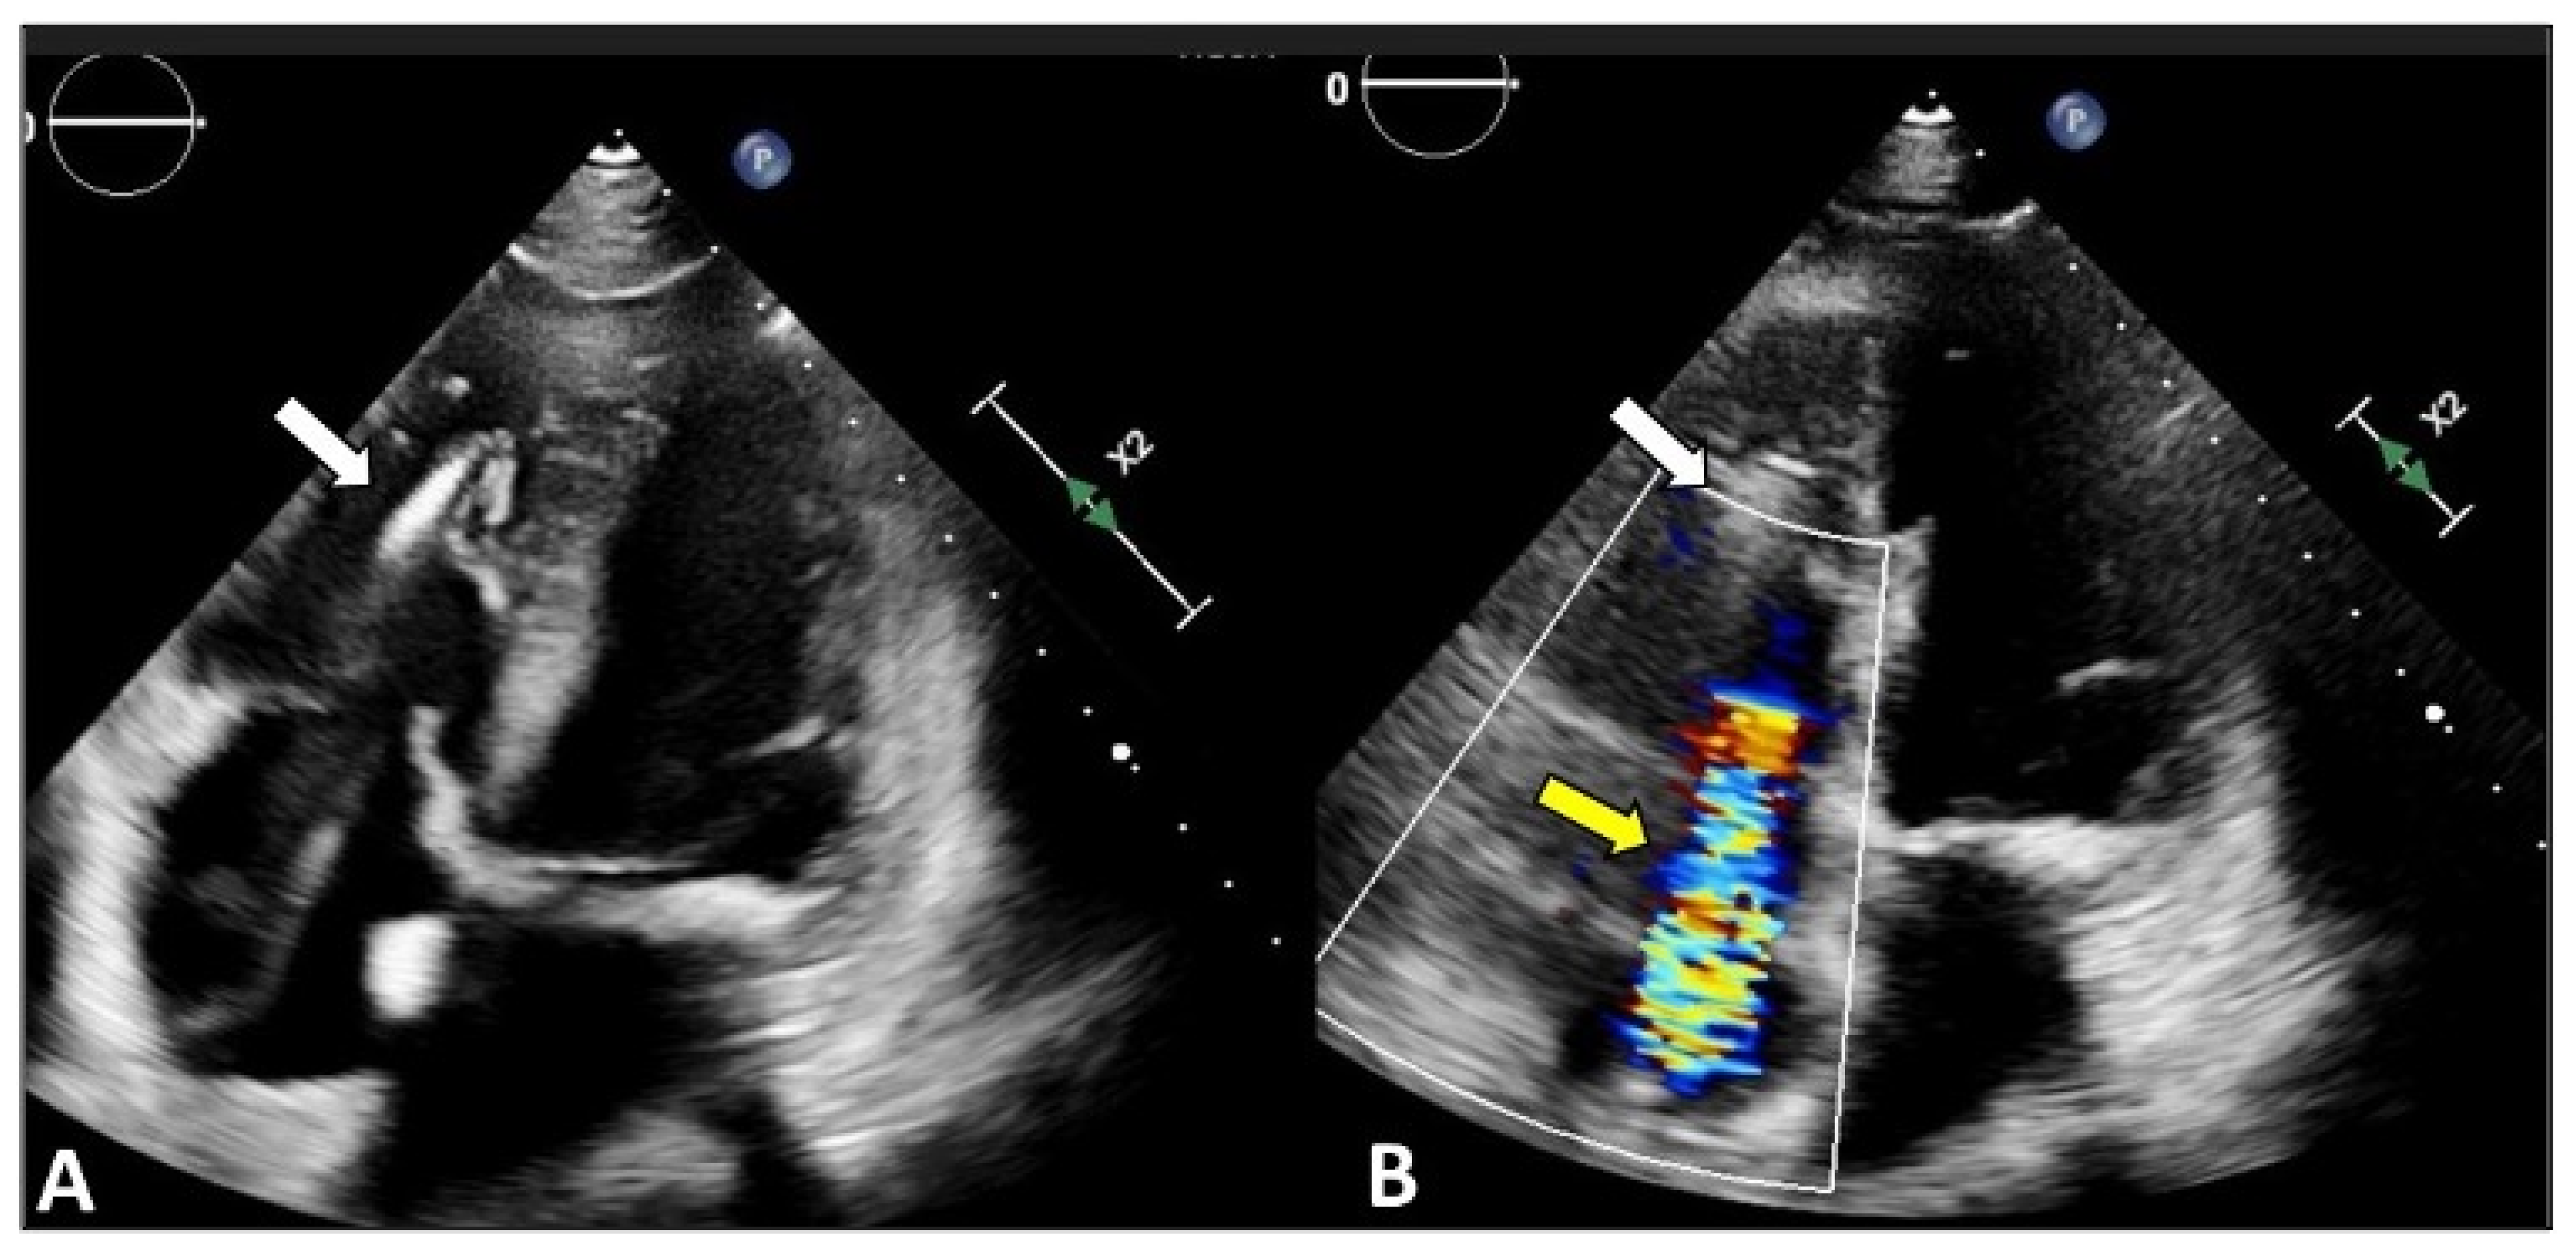

3.1. Two-Dimensional and Three-Dimensional Transesophageal Echocardiography

- Ro, R.; Tang, G.H.L.; Seetharam, K.; Khera, S.; Sharma, S.K.; Kini, A.S.; Lerakis, S. Echocardiographic Imaging for Transcatheter Tricuspid Edge-to-Edge Repair. J. Am. Heart Assoc. 2020, 9, e015682. [Google Scholar] [CrossRef] [PubMed]

- Agricola, E.; Ancona, F.; Stella, S.; Rosa, I.; Marini, C.; Spartera, M.; Denti, P.; Margonato, A.; Hahn, R.T.; Alfieri, O.; et al. Use of Echocardiography for Guiding Percutaneous Tricuspid Valve Procedures. JACC Cardiovasc. Imaging 2017, 10, 1194–1198. [Google Scholar] [CrossRef]